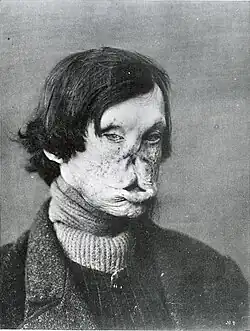

Face severely deformed by leprosy

Face severely deformed by leprosy -